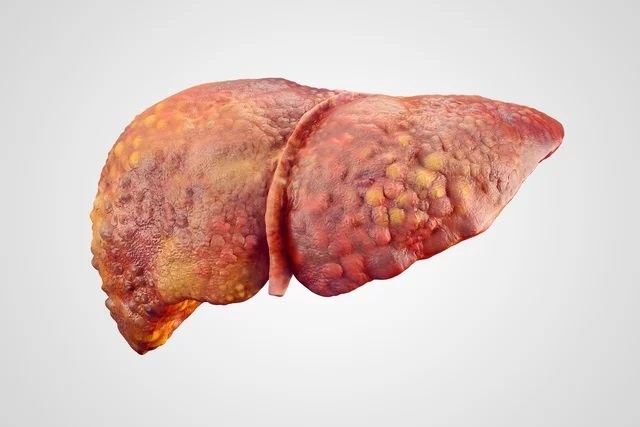

Nos estágios iniciais de gordura no fígado, condição chamada de esteatose hepática, normalmente não são percebidos sinais ou sintomas, no entanto à medida que a doença progride e há comprometimento do fígado, é possível que surjam alguns sintomas.

- Fezes esbranquiçadas.=Uma vez que nos graus mais leves da esteatose hepática não existem sintomas característicos, o diagnóstico normalmente acontece durante exames de rotina. O acúmulo de gordura no fígado geralmente não é uma situação grave, mas quando não é devidamente tratada, pode gerar perda de funcionamento das células do fígado e cirrose, podendo ser necessário fazer um transplante de fígado.

Possíveis causas de gordura no fígado

O mecanismo que leva ao acúmulo de gordura no fígado ainda não é muito bem estabelecido, apesar de ser muito estudado. No entanto, sabe-se que algumas condições favorecem o acúmulo de gordura nesse órgão, levando progressivamente à perda da função hepática. Pessoas que possuem maus hábitos alimentares, que não praticam atividade física, que fazem uso frequente e excessivo de bebidas alcoólicas, que tem colesterol alto ou que são diabéticas possuem maior chance de ter gordura no fígado. Saiba mais sobre as causas de gordura no fígado. Como tratar